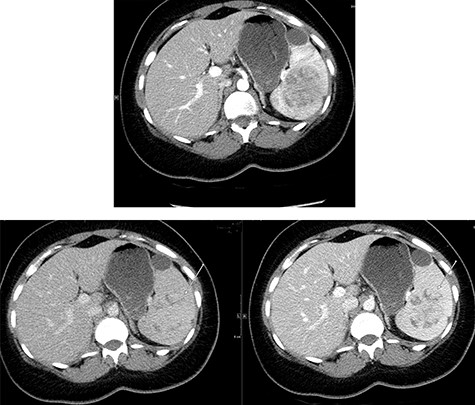

A multi-planar, multi-sequential abdominal magnetic resonance imaging (MRI) without contrast showed a well-circumscribed splenic mass with patchy nodular enhancement, which became more diffuse on delayed images and had low T2 signal and isointense T1 signal with no diffusion restriction (Fig. 3). There was no evidence of lymphadenopathy and no features favoring a lymphoma. The splenic mass was diagnosed as SANT, with plans to follow it with serial imaging.

(Top) coronal T2 WI MR Image showing a hypointense lesion in the spleen, which is not showing any diffusion restriction (right image); (middle images) post-contrast axial T1 WI MR image showing hypointense lesion with patchy contrast enhancement in the center (middle right image); the lesion becomes further isointense on delayed image (middle left image); (bottom) MRI of abdomen T1 weighted axial (bottom left) and coronal (bottom right) post-contrast images showing a lesion in the spleen (arrow) with peripheral and septal enhancement with a hypoenhancing center.